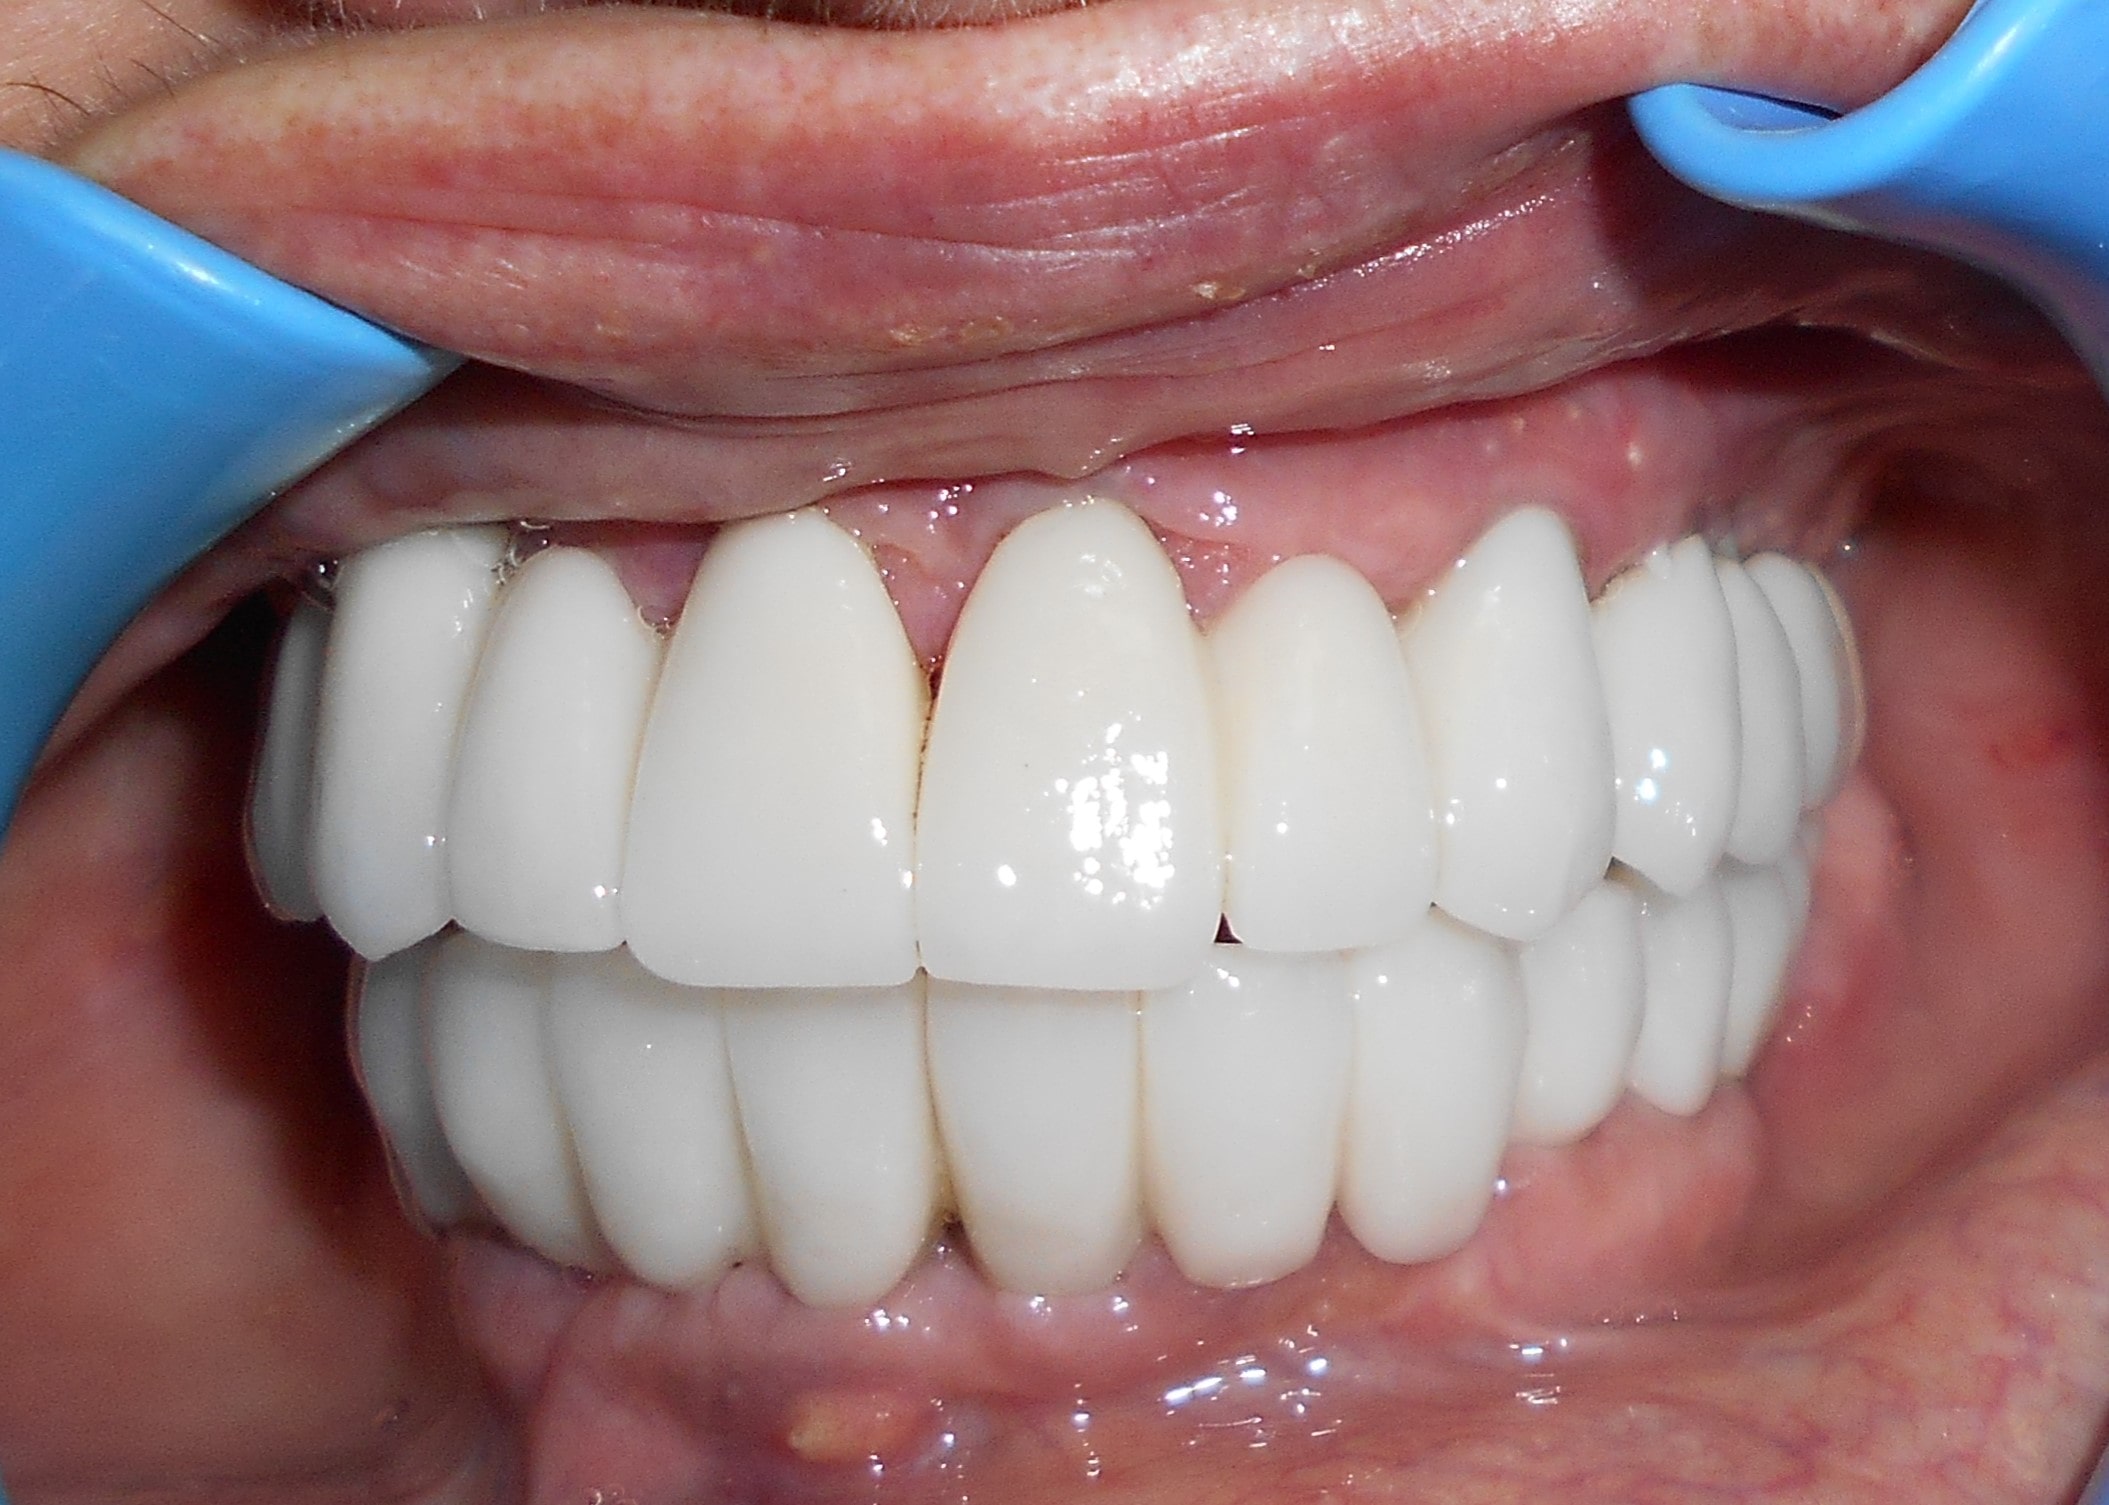

Pacijent 4

Pacijent iz inostranstva doalzi sa totalnom protezom u gornjoj vilici i sa uznapredovalom parodontopatijom preostalih zuba u donjoj vilici. Pacijent navodi da su mu u inostranstvu rekli da je nemoguće u gornjoj vilici ugraditi implantate bez velikih hirurških zahvata koji podrazumevaju transplantaciju kosti sa udaljenih delova tela i sinus lift proceduru. U gronjoj vilici je bila minimalna količina kosti sa izraženo spuštenim sinusima i sa minimalno vretikalnom i horizontalnom visinom kosti. Naše rešenje se sastojalo u sledećem: ugradnja deset implantata u gornjoj vilici u raspoloživu kost sa ugrdnjom veće količine veštačke kosti, od deset ugrađenih implanta dva implantata su tuberopterigoidna koji su zamenili sinus lift proceduru. U gornjoj vilici smo se opredelili za ugradnju većeg broja implantata kako bi prilikom izrade fiksnog protetskog rada dobili ravnomeran prenos pritiska žvakanja na implantate. U donjoj vilici intervencija je bila istovremena i ona je podrzumevala vađenje svih preostalih zuba i ugradnju osam implantata. Kompletno zbrinjavanje koje obuhvata hiruršku i protetsku fazu je trajalo tri meseca, tokom kojih je pacijent u gornjoj vilici bio zbrinut sa privremenom totalnom protezom, a u donjoj vilici sa fiksnim privremenim zubima koji su bili fiksirani na tek ugrađenim implantatima. Definitivni protetski rad je uspešno završen sa cirkonijum keramičkim - bezmetalnim mostovim pre četiri godine.